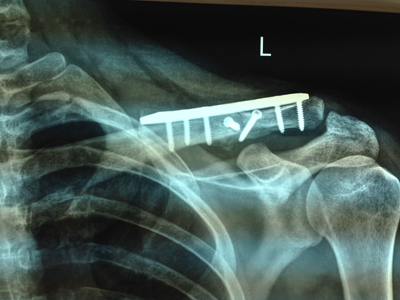

| Συντριπτικό κάταγμα κλείδας | Κάταγμα ώμου |